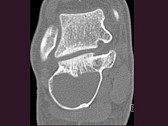

- 单项选择题男,32岁, 几天前踝部扭伤,疼痛, 不能行走,结合CT图像, 最可能的诊断是 ( )

A、骨囊肿

B、动脉瘤样骨囊肿

C、骨纤维异常增殖症

D、骨巨细胞瘤

E、畸形性骨炎